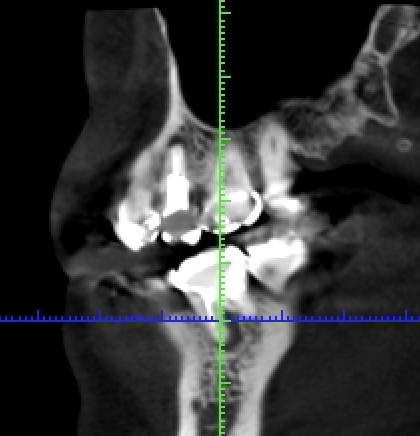

写真は同一部位のレントゲン写真とCT画像です。レントゲン写真は顎骨の形態や走行する神経の位置、歯が生えている方向把握することはできても2次元的な位置関係でしか把握できません。つまり歯や神経の位置がわかっていても実際にどのくらいの位置関係にあるのかを正確に判断することはレントゲン写真では不可能なわけです。しかし、歯科用CT画像では顎骨の形態や走行する神経の位置、歯の生えている方向、さらには骨密度の状態を3次元的に画像化する事が可能なため、より正確な診断する事ができます。